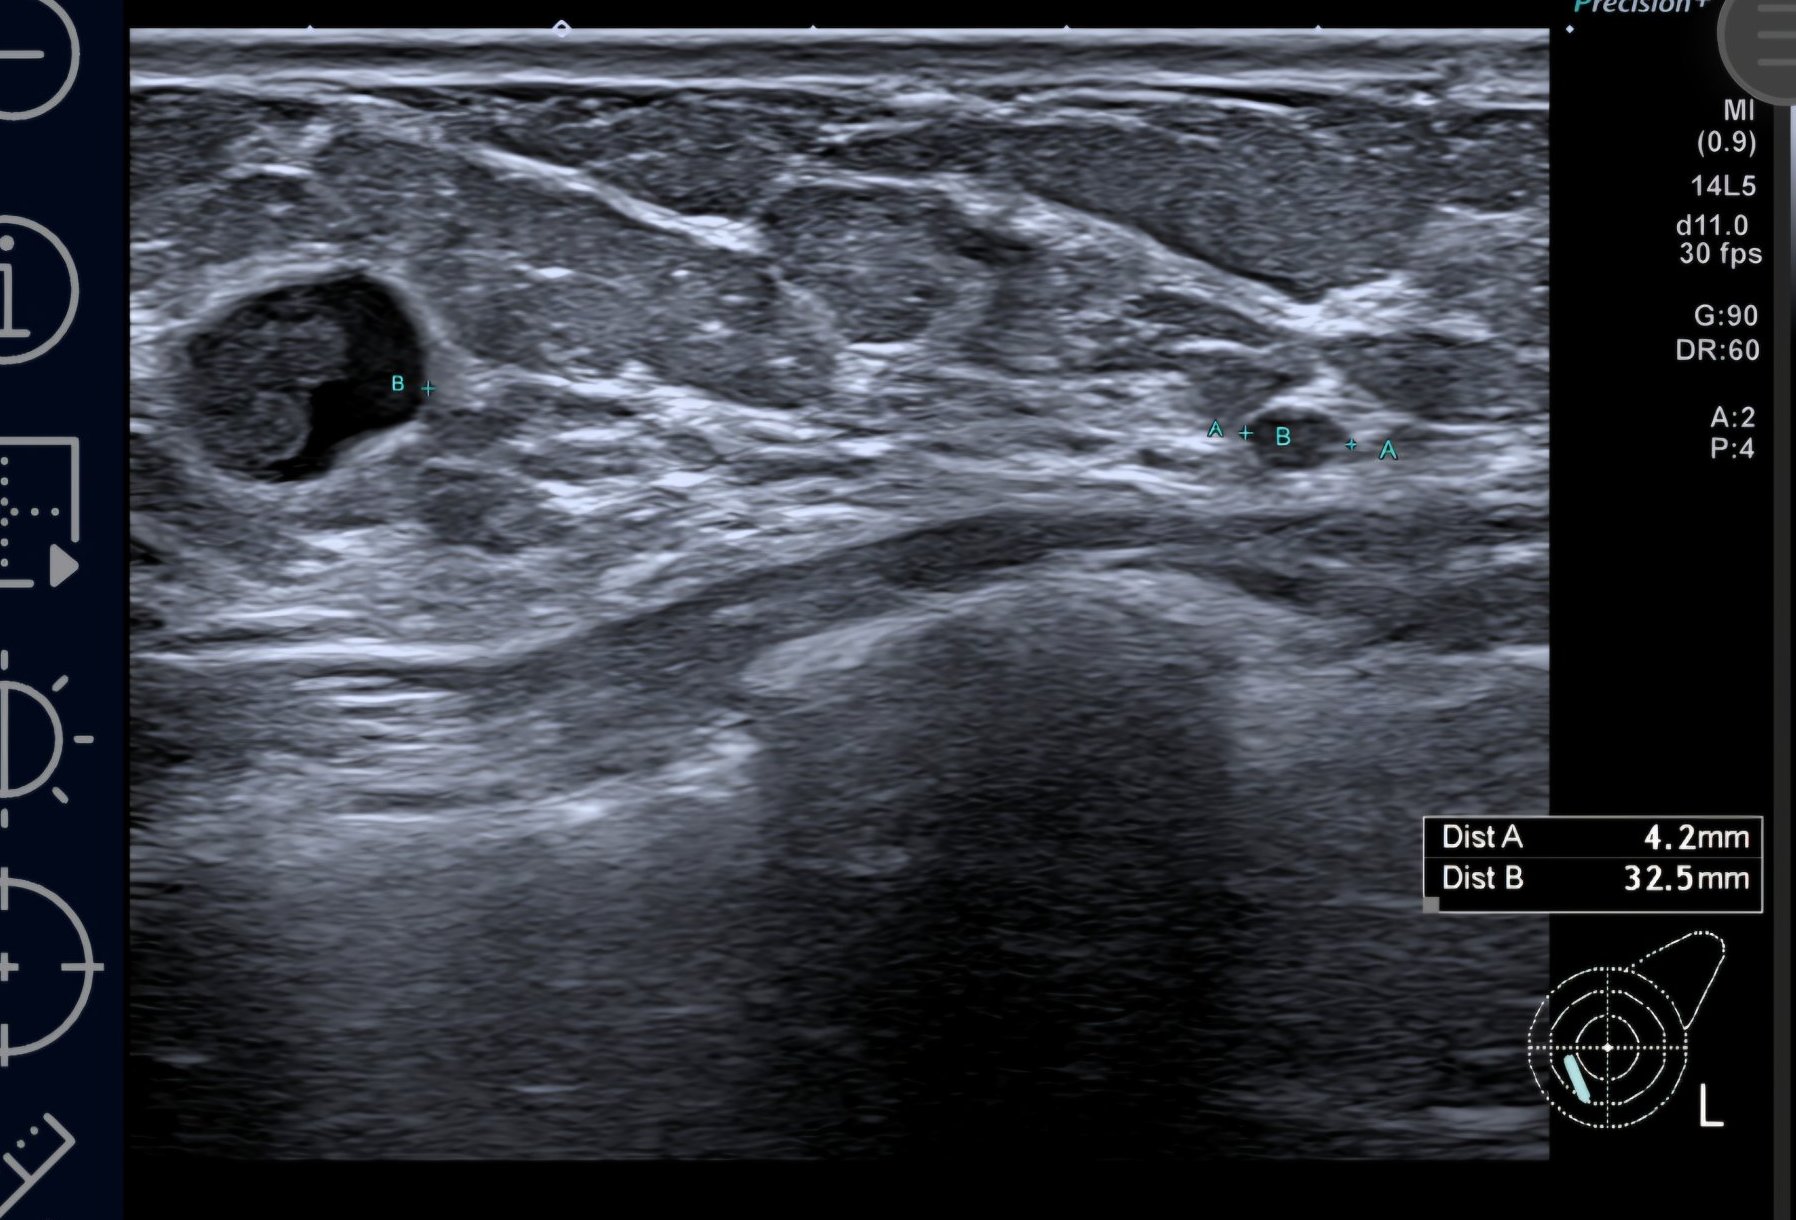

Далинда, ето малко картинки от BIRADS 4c ( най- вече вляво) , само по образни. Това са първите картинки, оттогава имам още нови попълнения. Биопсията не показа точно какво е и какво не е, според лекарите може би не са "уцелили" точното място в лезията, защото има известно разминаване. Вчера бях на ПЕТ, само сумтяха и ми казаха, че ще разбера резултатите от лекуващата другата седмица, след като е минала Туморната комисия 🤷‍♀️

Marie curie, твоето само по формата и е силно подозрително за рак. Неправилни, наръбени форми са червена лампа.